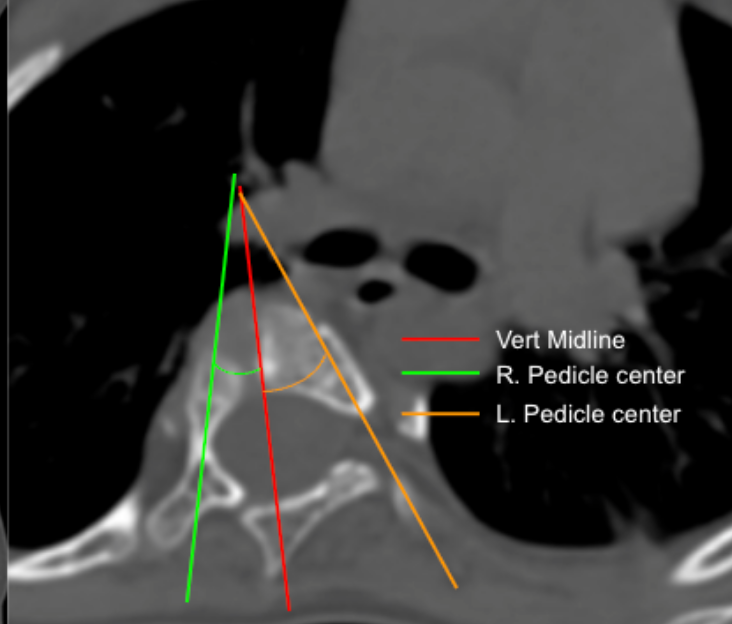

Facet Join Orientation and Tropism

Axial Rotation